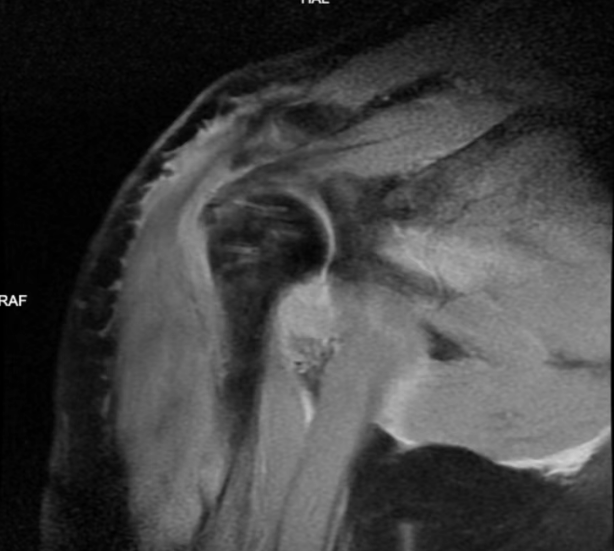

▲巨大肩袖撕裂,冈上肌腱已退缩止肩胛盂水平。

通过磁共振检查和查体,我们判断该患者存在冈上肌腱、冈下肌腱、肩胛下肌腱等三条肌腱的撕裂,而且冈上肌腱的断端已经回缩至肩胛盂水平,大结节结及肱骨头裸露,属于巨大的不可修复的肩袖撕裂。